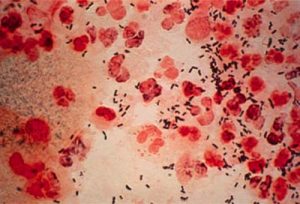

Bệnh lậu gây ra do khuẩn lậu có tên khoa học là Neisseria Gonorrhoeae. Đây là loại vi khuẩn có tốc độ lây lan nhanh chóng. Trung bình cứ 15 phút lại phân chia một lần.